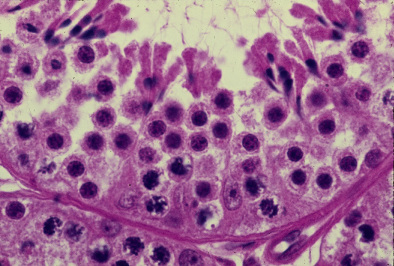

精巣10. 精子形成2.

サル、ブアン液で固定、パラフィン包埋、H-E染色、x 750.

ここに見られるのは分裂中の精粗細胞と精娘細胞と精子組織形成の途上の精子------

細胞である。画面中央下部に4個のセルトリー細胞が狭い間隔をおいて立ち並び、-

それぞれの左右に精娘細胞が接している。成熟分裂では、精娘細胞である期間は-----

短くて、精母細胞の分裂によって生じた精娘細胞は休止期を持つことなく、直ち----

に第二成熟分裂を行って精子細胞となる。従って切片標本上で精娘細胞を確認す----

ることは、必ずしも容易でない。「精巣8」で述べたように、精母細胞と精娘細胞----

が同一の区画内に共存することはなく、また精娘細胞と精子細胞とが同一の区画-----

内に共存することもない。この図で基底膜の近くに見られる分裂中期の核は、精-----

粗細胞の核である。--------------------------------------------------------------------------------

10. Spermatogenesis 2.

Monkey, fixation with Bouin’s fluid, embedding with paraffin, x 750.

are 4 or 5 spermatogonia in mitosis. Numerous round cells with middle-sized round

nucleus are all the secondary spermatocytes. The secondary spermatocytes perform

soon the second meiotic division to become spermatids (haploids). Thus coexistence--

of primary and secondary spermatocytes and also that of second spermatocytes and

spermatids, in one same component do not take place.---------------------------------------